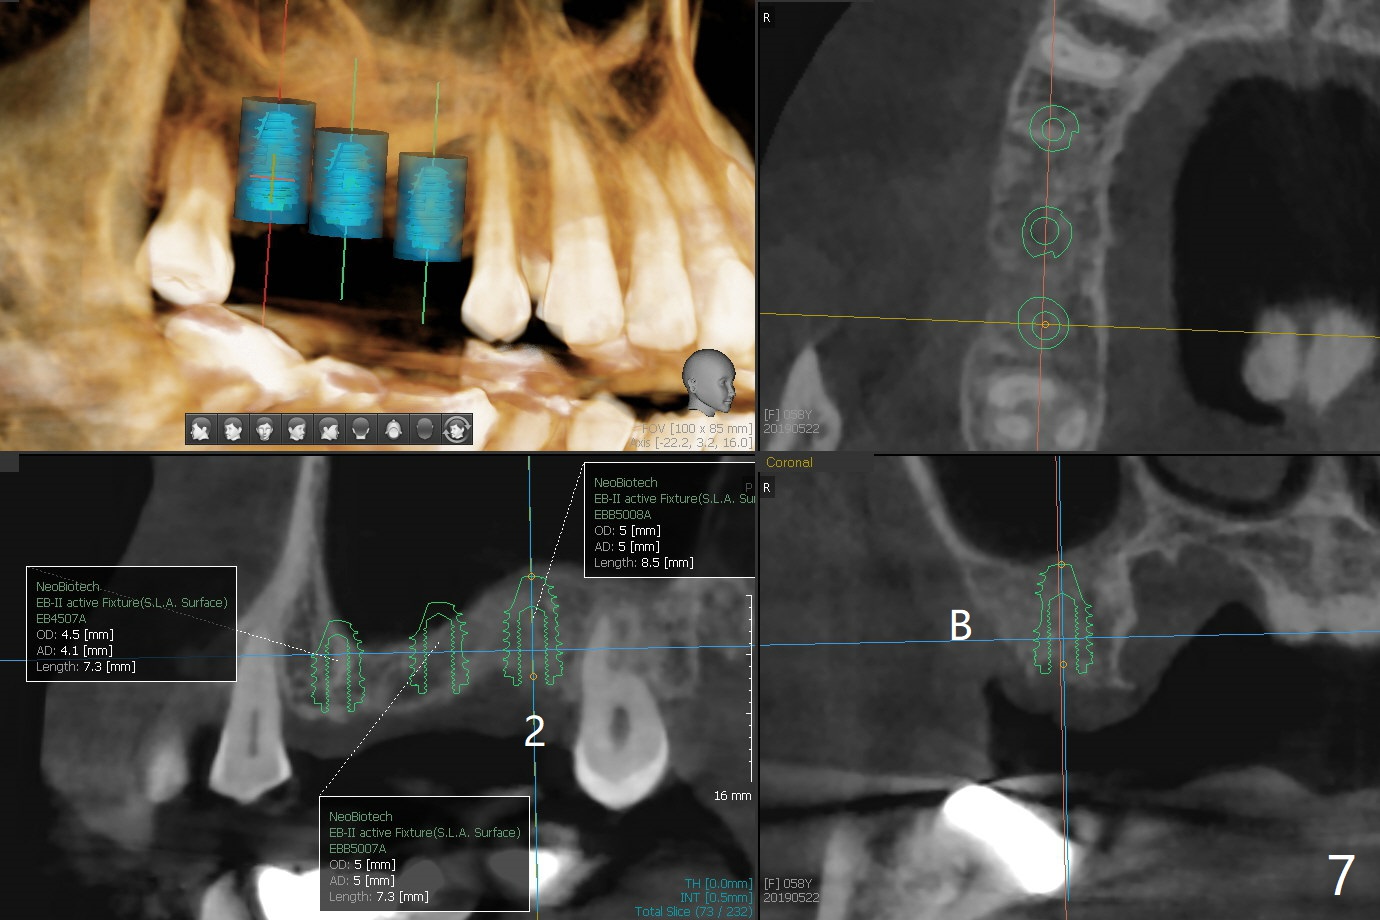

A 57-year-old woman returns with pain in the upper right quadrant (Fig.1,2). In fact the mesiobuccal root of the tooth #2 has vertical fracture. Although the socket destruction at #3 is not as extensive as that of #2, the socket of #3 has communication with the sinus. Prior to socket preservation, a piece of Osteogen plug is inserted at #3. PRF should be prepared for severe bone loss. In contrast there is no bone loss around the implants at #19 or #30 (Fig.1,3,4). Although the socket at #2 is slightly open 9 days postop, bone graft appears to be present (Fig.5). The bone at #2 and 3 seems to regenerate 7 months post socket preservation (Fig.6). Three short implants seem to be better than 2 implants for 3-unit FPD (Fig.7-9).